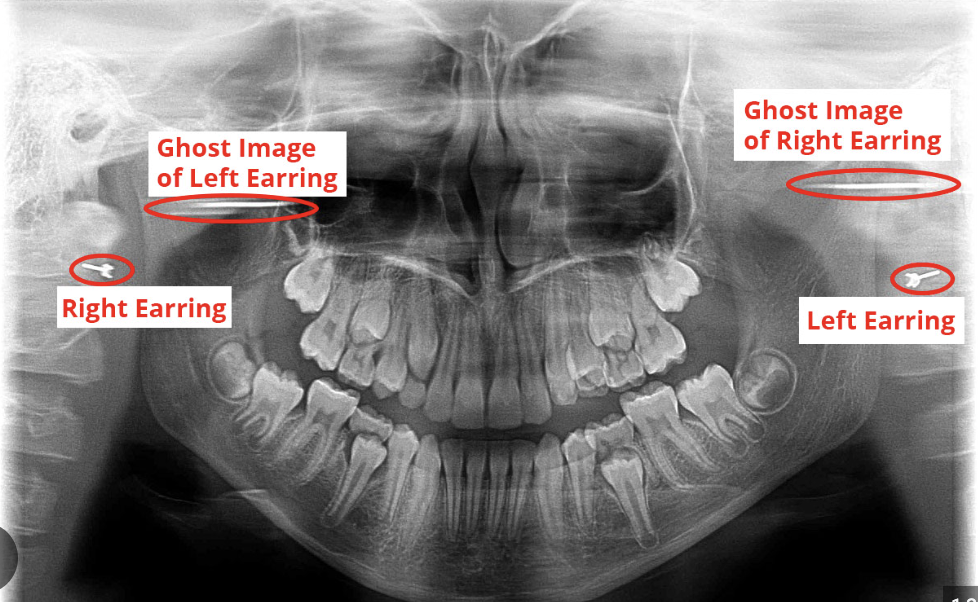

What is a ghost image?

This is when a real object on one side of the body is projected on the opposite side as more magnified, blurry, and higher up. It will have the same general shape as the object and will not be a mirror image.